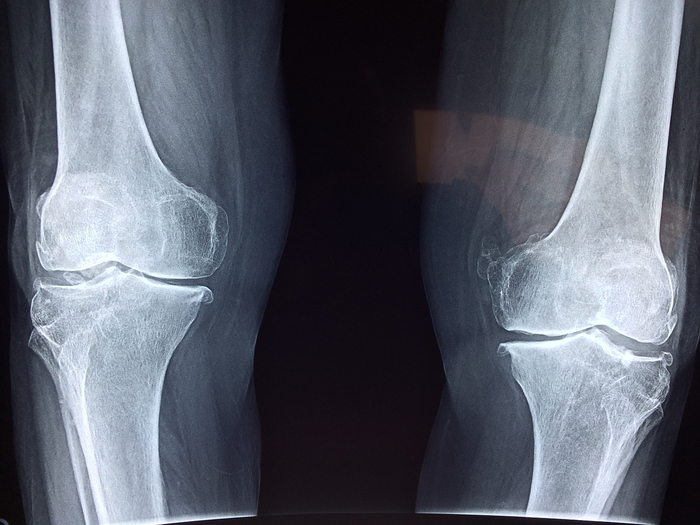

보다 심층적인 분석이 필요한 경우, MRI, X-ray, 초음파 검사 등 다양한 영상 진단법이 시행됩니다. 이러한 검사는 병변의 거의 모든 세부 사항을 파악할 수 있게 해줍니다. 특히 MRI는 연조직을 잘 보여주기 때문에 관절의 상태를 확인하는 데 유용한 도구로 간주됩니다.

- MRI(자기공명영상): 연골, 힘줄, 인대 등을 자세하게 볼 수 있습니다.

- X-ray: 뼈의 구조적 문제를 진단하는 데 효과적입니다.

- 초음파 검사: 수분의 유무, 염증 상태를 확인할 수 있습니다.